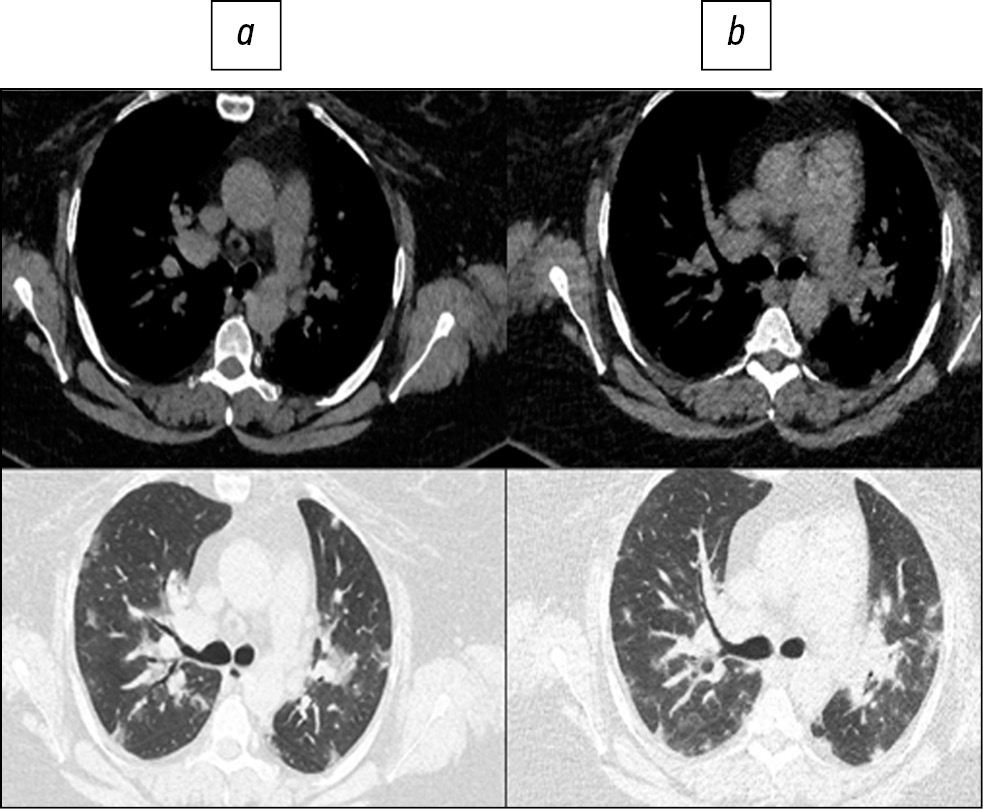

Fig. 1. Patient, 78 years old: standard computed tomography at admission was performed with a radiation load of 2.5 mSv (a), low-dose computed tomography - 1.0 mSv (b).

Here are illustrative examples of clinical cases (Figs. 1–6), demonstrating the similarity of diagnostic value of two aforementioned research methods. Columns on the left (a) show images of a standard CT scan performed upon admission of the patient to the hospital, and columns on the right (b) present LDCT over time. The top line of images indicates the pulmonary window mode, whereas the bottom line indicates the mediastinal window mode. For comparison, values of radiation exposure in each case are presented. Time intervals between standard CT and LDCT were 2–7 days; thus, the primary endpoint was reached in all patients enrolled in the study.